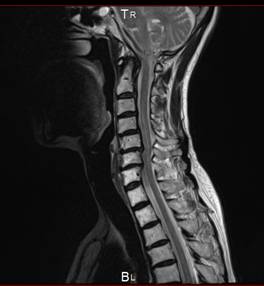

首頚椎椎間板ヘルニア専門HEADLINE

頚椎と腰椎ヘルニア 狭窄症 痛み シビレ 交通事故むち打ち治療自賠責